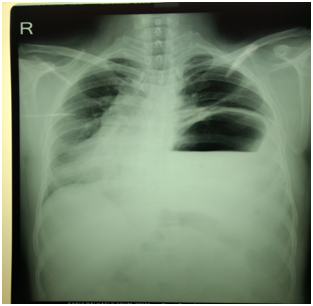

52 years male who is a chronic smoker with systemic hypertension was referred to our center for management of acute ST elevation anterior wall MI. He was managed in outside cardiac center with thrombolysis with streptokinase. Patient gives the past history of thoracotomy for repair of diaphragmatic hernia. On clinical examination, vitals were stable. Cardiovascular system (CVS) examination: Apex localized to the right 5th intercostal space. There was decreased air entry over the left inter/infrascapular and axillary lung zones. Chest X-ray was suggestive of elevation of left dome of diaphragm with fundus air shadow with dextrocardia (apex pointed to right side with right sided aortic knuckle) (Figure 1). Electrocardiogram was suggestive of dextrocardia (decreasing voltages from V1-V6) as shown below in Figure 2. Echocardiography showed dextrocardia with mild LV systolic dysfunction (LVEF-40%) with regional wall motion abnormality (RWMA) along LAD territory. Troponin I was positive (0.1ng/ml) and CPK-MB was 80IU/L. Coronary angiography was done with Judkins left and right (JL and JR) 3.5×6F diagnostic catheter. It revealed single vessel disease over mid-LAD (90% stenosis) as shown in Figure 3. Subsequently, left coronary artery was hooked with EBU 3.5×6F catheter. BMW wire was used to cross the lesion followed by multiple predilatations with 2×10 mm balloon. Successful PCI was done with deployment of NOVUS drug eluting stent (Sirolimus eluting stent) 2.75×32mm at 14atm.pressure as illustrated in Figure 4. 150 ml of contrast (non-ionic, iso-osmolar Iohexol) was used during the procedure. TIMI III flow was achieved. During shifting of the patient to the coronary care unit (CCU), patient had accelerated hypertension with increasing shortness of breath and desaturation(Sp02<90%) which was suggestive of acute pulmonary edema. The patient responded with diuretics, nitroglycerin infusion, morphine and high flow oxygen support within hours. Patient was discharged on fourth day in stable condition.

Figure 1: Chest X-ray of an anterior wall MI patient with isolated dextrocardia with left dome of diaphragm elevation following thoracotomy.